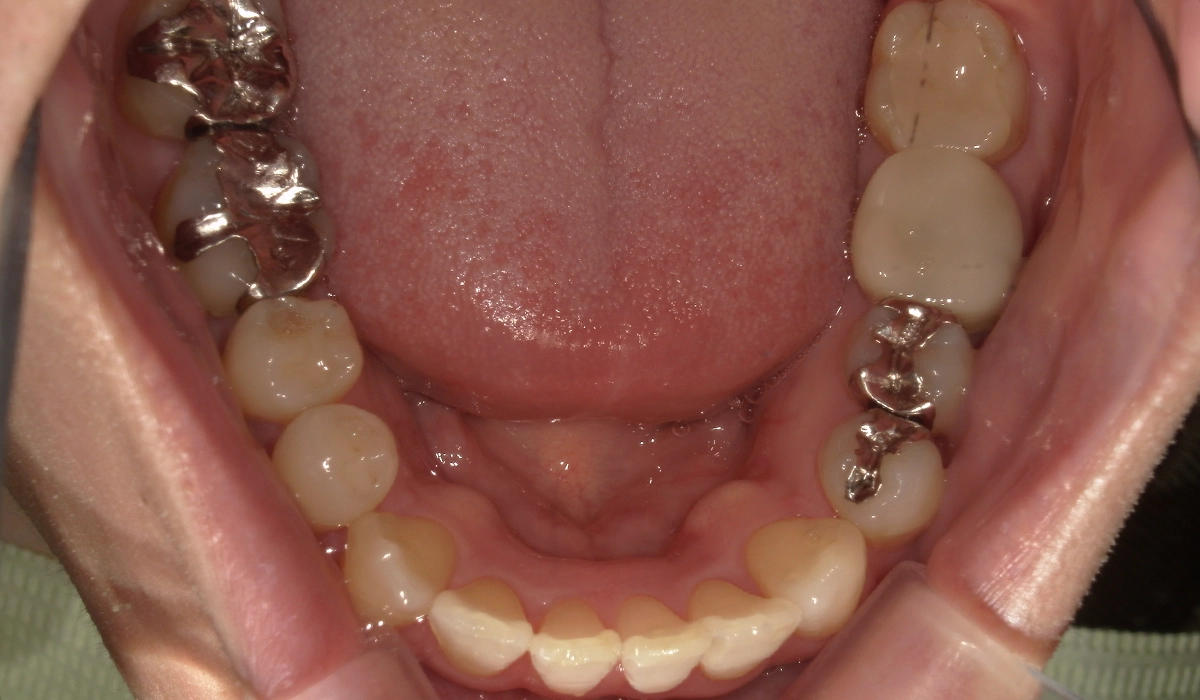

術後:上顎

術後:下顎